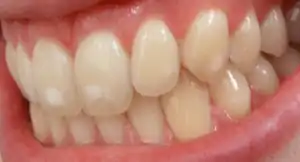

It appears as a range of visual changes in enamel[4] causing degrees of intrinsic tooth discoloration, and, in some cases, physical damage to the teeth. The severity of the condition is dependent on the dose, duration, and age of the individual during the exposure.[1] The "very mild" (and most common) form of fluorosis, is characterized by small, opaque, "paper white" areas scattered irregularly over the tooth, covering less than 25% of the tooth surface. In the "mild" form of the disease, these mottled patches can involve up to half of the surface area of the teeth. When fluorosis is moderate, all of the surfaces of the teeth are mottled and teeth may be ground down and brown stains frequently "disfigure" the teeth. Severe fluorosis is characterized by brown discoloration and discrete or confluent pitting; brown stains are widespread and teeth often present a corroded-looking appearance.[1]

| Normal | 0 | The enamel represents the usual translucent semivitriform (glass-like) type of structure. The surface is smooth, glossy and usually of pale creamy white color |